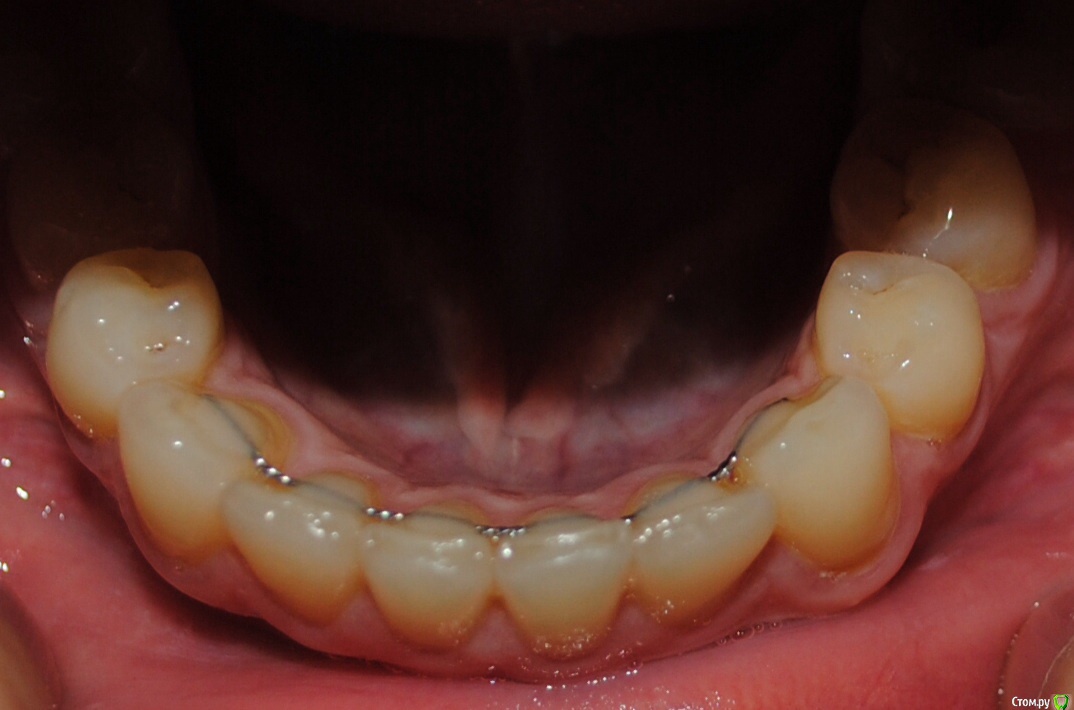

Алина-малина Опубликовано 4 августа, 2015 Поделиться Опубликовано 4 августа, 2015 Здравствуйте, уважаемые специалисты! Подскажите пожалуйста, как можно исправить эту ситуацию? Можно ли обойтись без брекетов? После ношения брекетов стал наклоняться клык вовнутрь. Стоит несемный ретейнер. Ортодонт утверждает что все в порядке и надо делать лоскутную операцию(( Ссылка на комментарий

Yana guapa Опубликовано 4 августа, 2015 Поделиться Опубликовано 4 августа, 2015 Подскажите пожалуйста, как можно исправить эту ситуацию? Можно ли обойтись без брекетов? После ношения брекетов стал наклоняться клык вовнутрь. если клык стал уходить во внутрь - значит что то его туда толкает. как правило, верхний клык (его позиция и наклон). За какой срок произошло изменение после снятие брекетов? Если реально беспокоит - то повторное ношение брекетов с правильным конечным взаимоотношением зубов (если это возможно сделать в силу различных факторов ). Ссылка на комментарий

Алина-малина Опубликовано 15 августа, 2015 Автор Поделиться Опубликовано 15 августа, 2015 Спасибо что ответили. Клык стал уходить через пол года после снятия. Брекеты носила 8 месяцев. Неужели теперь снова брекеты??? Возможно ли хотя бы на одну челюсть? Ссылка на комментарий

Yana guapa Опубликовано 15 августа, 2015 Поделиться Опубликовано 15 августа, 2015 Спасибо что ответили. Клык стал уходить через пол года после снятия. Брекеты носила 8 месяцев. Неужели теперь снова брекеты??? Возможно ли хотя бы на одну челюсть?если на одну челюсть - то и исправится на одной. логично же. а если у Вас на двух челюстях неровно стоят клыки - то на две и ставить надо. чудес не бывает. Вначале выровнять верхнюю, и тогда появится возможность выровнять нижнюю челюсть Ссылка на комментарий